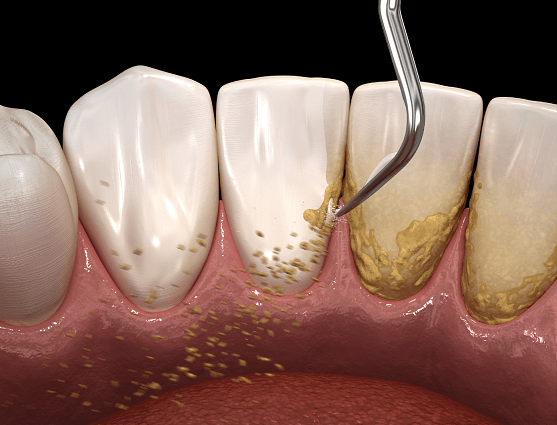

Understanding Gingivitis, Periodontitis, and the Importance of Gum Treatment

Gingivitis and Periodontitis

Gingivitis is an early stage of gum disease, marked by symptoms like redness, swelling, and bleeding of the gums. It is often caused by plaque buildup on the teeth. If not treated, gingivitis can progress into periodontitis, a more advanced form of gum disease where the infection affects the deeper tissues supporting the teeth. Periodontitis can lead to complications, including tooth mobility and gum recession, if not addressed.

Why Gum or Periodontal Treatment Is Needed

Gum treatment or periodontal treatment is necessary to manage gum disease and prevent further progression. Early intervention may help reverse gingivitis and stop it from advancing to periodontitis. For more advanced stages of periodontitis, treatment focuses on removing plaque and tartar from beneath the gumline, aiming to reduce infection and restore gum health.

Gum Scaling

How Gum Treatment Is Performed

Gum treatment often starts with a professional cleaning known as scaling and root planing. This involves removing plaque and tartar from below the gumline. In more advanced cases, surgical procedures may be required to clean deeper areas affected by the disease. The goal of periodontal treatment is to improve gum health and manage the condition of your gums effectively.